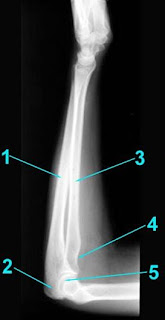

Keterangan

gambar:

1. Os ulna

2. Olecranon

3. Os radius

4. Radial tuberosity

5. Trochlear joint